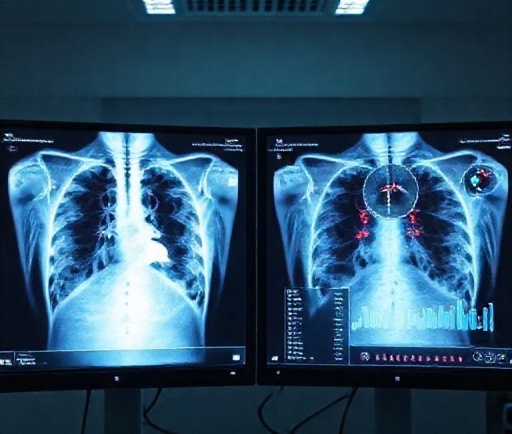

AI 기반 의료영상 진단: 시장 전망·비즈니스 모델·도입 전략

AI 기반 진단·의료영상 분석 🧠🖥️

시장 전망: 영상의 판독 보조, 이상 소견 자동탐지 등 AI 진단 보조도구 수요가 늘어요. 규제 승인 사례도 점차 증가하고 있습니다.

비즈니스 모델: SaaS(병원구독) · 라이선스(의료기기 승인 후) · API 제공.

필요 역량: 의료영상 처리, 딥러닝 모델, 임상 검증 및 규제 대응 능력.

시작 팁: 특정 영상(예: 흉부X선, 피부병변)으로 특화해 정확도를 높이고, PACS 연동 테스트를 통해 병원 도입 장벽을 낮추세요. 검증된 성능 수치와 실제 사례를 제시하면 영업이 쉬워집니다.